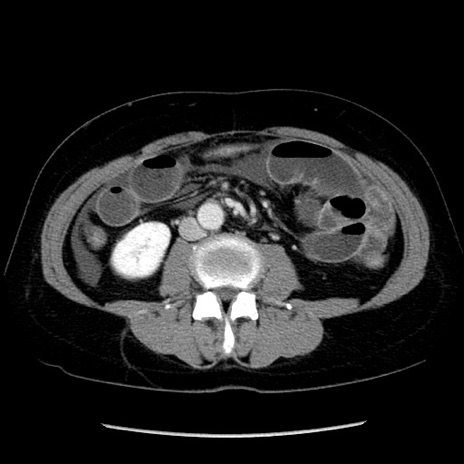

症例6(横断像)

【症例】50歳代女性

【主訴】下腹部痛

【現病歴】本日朝より下痢2回あり。 昼食を食べた後、嘔吐3回、下腹部痛認め、症状軽快せず、当院救急搬送。

最終食事:本日昼(生ものなし)。 昨日の夜、刺身を食ぺたとのこと。周囲に同様の症状の者なし。普段、排便は毎日あるとのこと。

【既往歴】卵巣癌術後(8年前に当院で卵巣摘出)

【身体所見】 意識清明、腹部:平坦、腸蠕動音→、やや硬、下腹部自発痛・圧痛あり、反跳痛あり、筋性防御なし。

【データ】WBC 16000、CRP 0.01